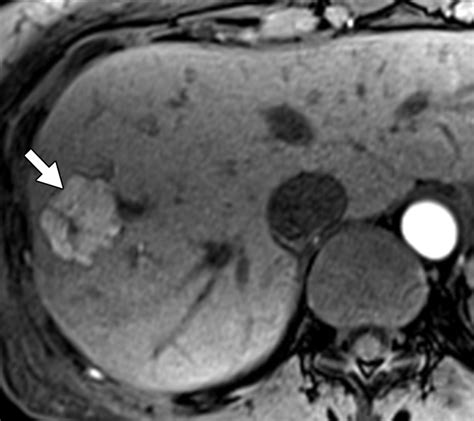

The hallmark of Focal Nodular Hyperplasia is the presence of a central fibrous scar. When radiologists view this mass through imaging technology, this central scar is a key diagnostic feature that helps distinguish it from other types of liver growths, such as hepatocellular adenomas or malignant carcinomas.

• MRI (Magnetic Resonance Imaging): This is the gold standard for diagnosing Focal Nodular Hyperplasia. Using specific contrast agents (like gadoxetate disodium), doctors can observe the unique way the mass absorbs and excretes the contrast, which is highly characteristic of FNH.